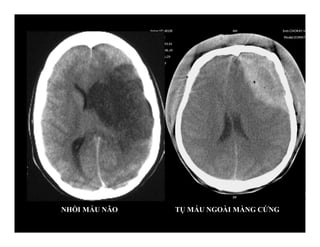

NHỒI MÁU NÃO TỤ MÁU NGOÀI MÀNG CỨNG

NHỒI MÁU NÃOTỤ MÁU NGOÀI MÀNG CỨNG